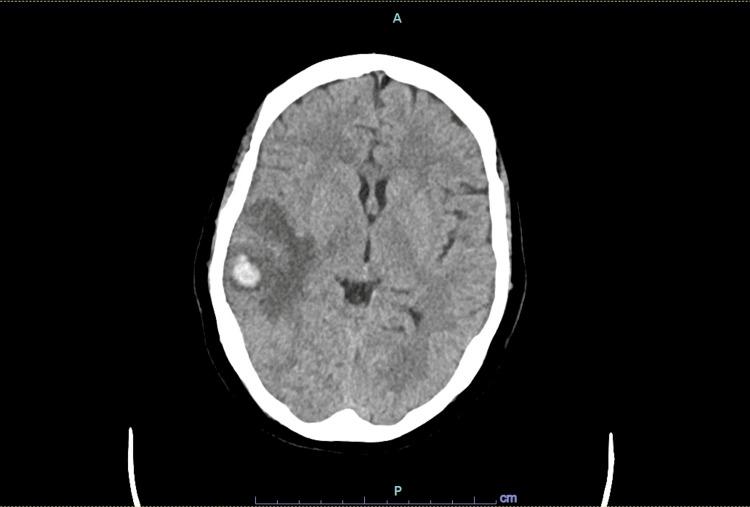

严重脱水引发的脑静脉窦血栓形成

Cerebral Venous Sinus Thrombosis Triggered by Severe Dehydration.

Cerebral venous sinus thrombosis (CVST) is the causative factor in a small proportion of strokes. It primarily affects individuals aged less than 55 years, with up to two-thirds of cases affecting females. It can be precipitated by a myriad of transient or permanent risk factors that result in a prothrombotic state. Diagnosis of CVST requires a high index of clinical suspicion as the presenting symptoms are often vague and include headaches, visual deficits, seizures, etc. Computed tomography or magnetic resonance venography are sensitive imaging diagnostic modalities. The majority of patients have a favorable prognosis. It is important to pursue thrombophilia work-up after the resolution of an acute episode as some cases are secondary to an underlying malignancy.

摘要

脑静脉窦血栓形成(CVST)是一小部分中风的致病因素。它主要影响年龄小于55岁的个体,高达三分之二的病例为女性。它可由导致血栓形成前状态的众多短暂或永久性危险因素引发。CVST的诊断需要高度的临床怀疑指数,因为其表现症状往往模糊,包括头痛、视力缺陷、癫痫发作等。计算机断层扫描或磁共振静脉造影是敏感的影像学诊断方法。大多数患者预后良好。在急性发作缓解后进行血栓形成倾向检查很重要,因为有些病例继发于潜在的恶性肿瘤。